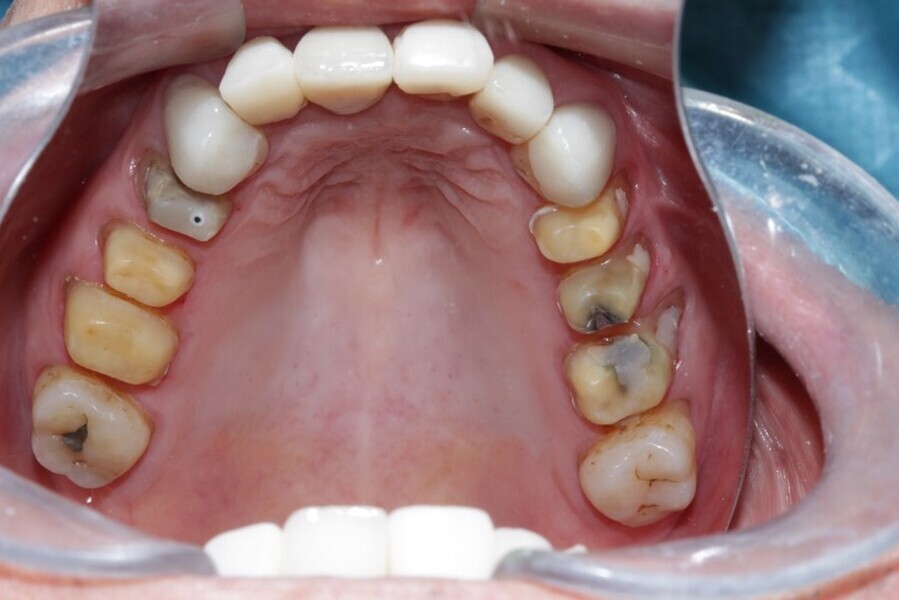

Figure 31 Occlusal view maxillary